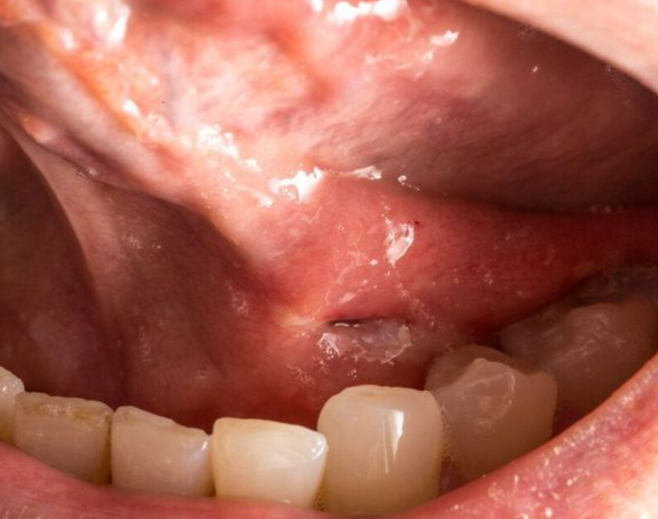

설암은 혀의 옆면, 바닥, 뿌리 등의 부분에 분포하고 있는 편평상피세포에 암이 생기는 것이에요.

이 암으로 발생하는 혓바닥 안쪽 통증과 같은 증상은 초기에는 증상이 가볍고 구내염과 매우 유사해서 착각하는 경우가 많아요.

✔️ 혀 안쪽 하얀 껍질, 붉은 반점의 2주 이상 지속

✔️ 궤양 부위가 점점 커지거나 고름 및 출혈 발생